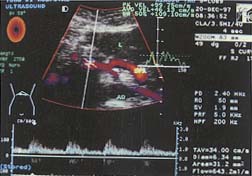

仪器与方法 仪器选用Diasonics Gate-Way ⅡD型电脑彩色多普勒诊断仪,超宽频凸阵探头,频率范围3.5~5MHz,所得资料经仪器光盘存储并录像。所有患者均前晚8时至第二天上午检查前禁食,取仰卧位,通过不同适当断面检测肝内病变的二维及血流信号后,放大显示肝总动脉(CHA)纵轴,将取样点尽量放在靠近肝总动脉的起始处(距起始点1.5cm以内),并测其内径,多普勒取样容积调至稍小于管腔(约为管腔的2/3),取样角度控制在60°以下,摒气获得满意频谱后,测时间平均速度(TAV),由仪器自动测出CHA的血流量,然后自动或手动测定PS、ED、RI。门静脉测量取肝门部门脉主干,均于呼吸末屏气后测量,具体方法同CHA。肠系膜上动脉(SMA)测量取样点位于距起始部约2cm处,方法同CHA。全部测量重复三次以上取平均值,所测频谱为显示好且至少显示三个以上心动周期(见图1~3)。

图3 在肠系膜上动脉距起始部约2.0cm处测定各项血流参数